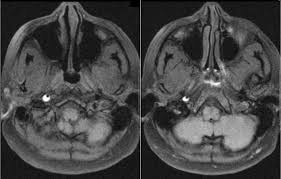

Carotid artery dissection (concept id: Each common carotid artery has an internal and an external branch. Carotid artery dissection is a tear in one of the layers of the artery wall. Spontaneous dissection of the carotid artery occurs in 3 per 100,000 of the population annually (1). It manifests with headache, neck pain, temporary vision loss, and/or ischemic stroke. This causes bleeding into the artery wall. Commonest in those in their mid 40s but seen at any age. Roller coasters are also a no no. Blood vessel walls normally have three layers, and a tear in any of these can allow blood to flow into the resulting space, causing the vessel to bulge. The first portion of each carotid artery is the called the common carotid artery. Carotid artery dissection is a major cause of cerebral infarction in the young. Mr signal of the mural hematoma has a similar temporal evolution than intracerebral counterpart. A carotid dissection can be due to injury.